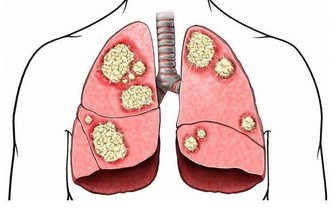

導語:而且他汀類的藥物還可以幫助改善血管內皮的功能,起到抗炎症和抗氧化的效果,所以他汀類的藥物不僅能夠幫助患者調節穩定血脂,還可以抑制血管內皮炎症反應,幫助穩定粥樣斑塊,

他汀類藥物的主要作用就是調節血脂穩定斑塊